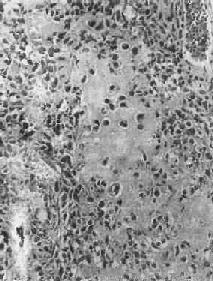

镜下,肿瘤主要由单核基质细胞及多核巨细胞等两种细胞组成(图17-6),间质血管丰富。基质细胞为梭形、卵圆形或圆形,细胞境界不清楚,常见胞浆突起。细胞核较大,染色质量中等,可具有一个核仁。多核巨细胞常较均匀地散布在基质细胞之间,是为本瘤的特点。多核巨细胞的直径常为30~60μm,核数一般为15~20个,最多可达100个以上,常聚集在细胞的中央。核的形态与单核基质细胞相似。细胞边界不规则,但分界较清楚,胞浆丰富,略呈嗜碱性,有时还可见含大量脂类的泡沫细胞。本瘤间质血管丰富,有多少不等的胶原纤维。肿瘤本身无成骨现象,但有时见有类骨组织及新生骨小梁,常见于纤维组织的周围,可能是一种反应性新骨形成或病理性骨折后形成的骨痂。

图17-6 骨巨细胞瘤(Ⅰ级)

肿瘤由大量基质细胞和多核巨细胞两种细胞组成